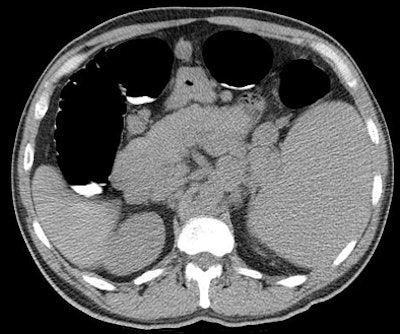

![]() |

| Image demonstrates splenomegaly and massively enlarged lymph nodes in a patient with unsuspected non-Hodgkin's lymphoma. |